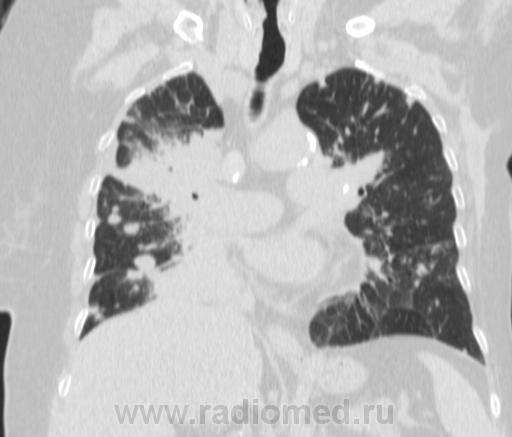

Метастатическое поражение легких.

Пожилая женщина, 76 лет находится на стац.лечении, провели СКТ дообследование.  Сопут- сr левой молочной железы. Такие множественные

поражения  в легких встречаются не часто.

Раннее несколько лет назад оперирована по поводу рака левой молочной железы.

Ну да, неспокойная работа, один тяжелее и  интересней другого. На обзорной рентгенограмме было всё видно прекрасно. Но терапевты направили, а я и не отказалась, чтобы в следующий раз знать- какие они бывают вторичные поражения легких.

Не всё на снимках видно. Многое осталось бы за кадром.